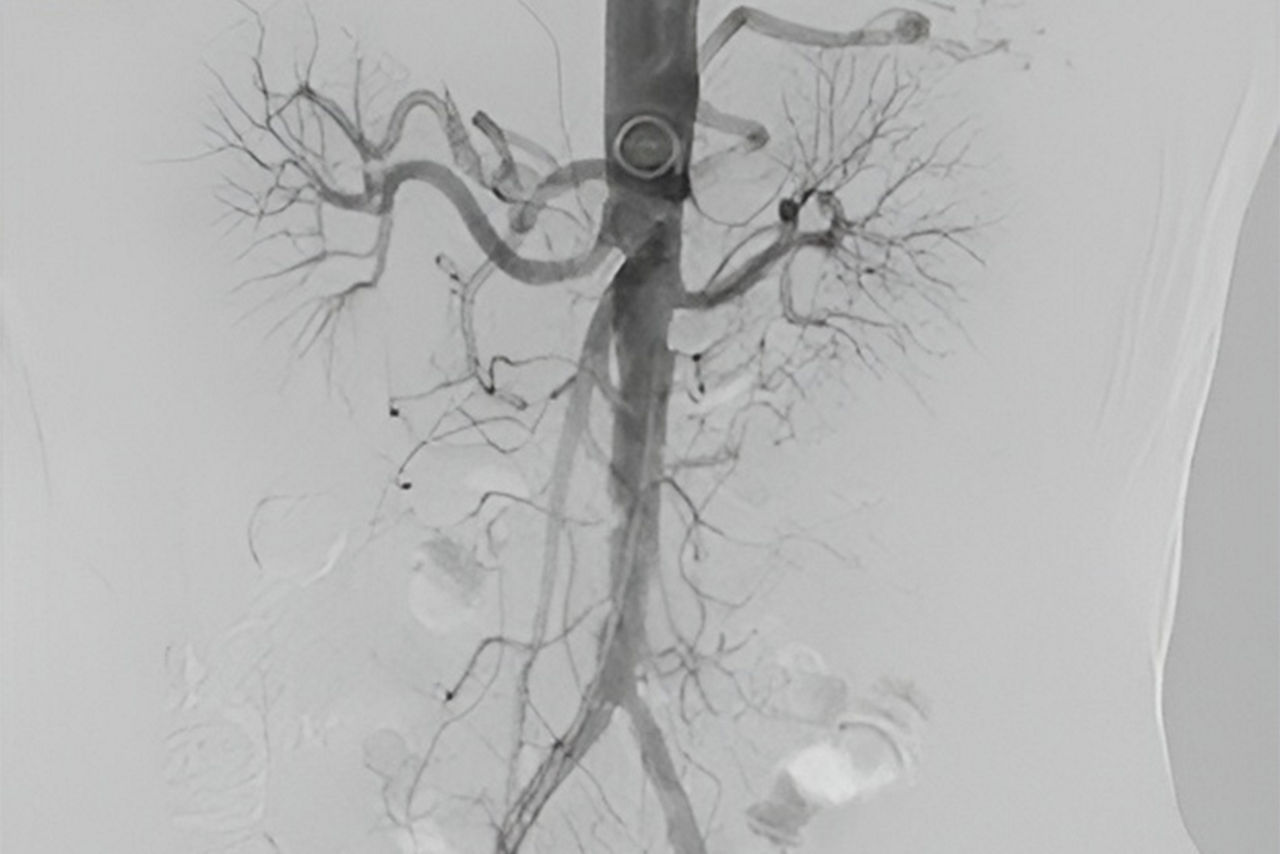

Access

Use DSA images on larger Field Of View to image the entire anatomy of interest.